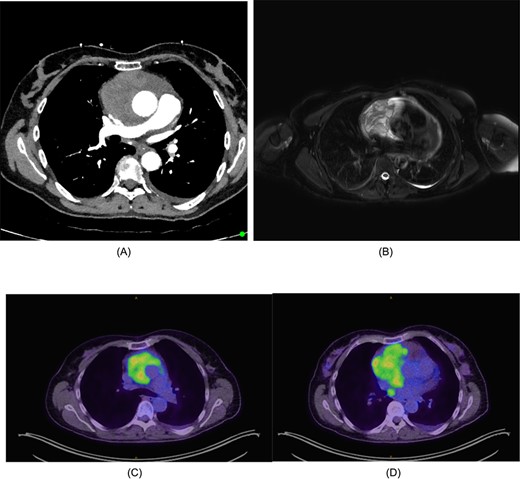

(A) CT chest/abdomen/pelvis demonstrating pericardial mass. (B) Cardiac MRI displaying cystic mass in the pericardium with small amount of pericardial fluid surrounding the lesion. (C) FDG-PET from the vertex to the upper thighs illustrating infiltrative lesion centred within the mediastinum. Small left pleural effusion noted. (D) Further focus of activity within the posterior mediastinum in the right para-oesophageal region.

The mass had a solid-cystic appearance on cardiac magnetic resonance imaging (CMRI) (Fig. 1B) encasing the aorta circumferentially and occupying the anterior and middle mediastinum. This lesion was intensely FDG-Avid on positron emission tomography (PET), with an isolated right para-oesophageal nodal metastasis (Fig. 1C and D).